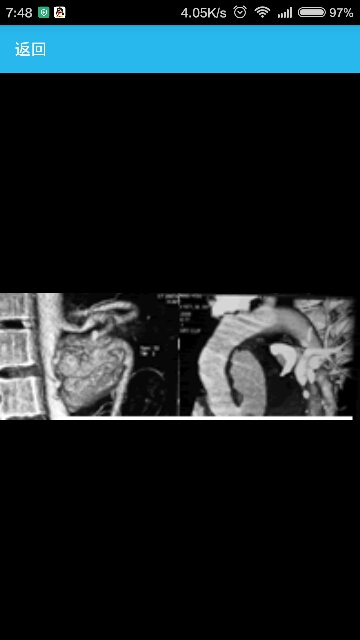

女性,42岁,因“进食后右季肋部疼痛,体重下降伴随阻塞性黄疸4个月”入院。临床表现患者右上腹有一触痛肿块。 辅助检查生化检验显示与梗阻性黄疸改变一致(胆红素76μmol/L,碱性磷酸酶653U/L,谷丙转氨酶281U/L,γ谷氨酰转移酶(γGT)1792U/L)。腹部超声(USS)提示厚壁胆囊胆结石及肝内胆管扩张,但无胆总管(CBD)结石或哈特曼氏囊(胆囊颈部的囊)嵌顿结石。磁共振胰胆管成像(MRCP)提示在肝总管狭窄上方还存在肝内胆管扩张,未见与之相关的胆结石。内镜逆行胰胆管造影(ERCP)示肝门狭窄且已置入支架。冲刷细胞学检查阴性。患者的黄疸状况得以解决。计算机断层扫描(CT)示胆囊窝周围肿块和环形钙化。肿块扩至肝外累及十二指肠并伴有门静脉及其左,右分支包绕肝门。虽然也考虑Mirizzi综合征的可能,但形态被认为与晚期胆囊癌一致。患者随后出现黑便,贫血并输血4个单位。 食管胃十二指肠镜检(OGD)证实出血来自于壶腹部(胆道出血),无消化性溃疡。动脉造影证实一个肝右动脉分支上有一3厘米大小动脉瘤,CT显示肿块中间部位。动脉瘤栓塞成功。两次CT引导下经皮穿刺肿块活检,其结果显示不是肿瘤而仅仅是急性炎症组织及坏死组织。由于不确定其恶性进程的存在,于是进行了剖腹探查。进入坏死的肝肿块,可见大量机化血栓及结石从肝右叶排出。 诊断:MirizziⅡ型综合征。 治疗对胆囊进行了切除。探查中发现一个4厘米大小的胆结石由胆囊管通过窦道进入肝总管从而导致MirizziⅡ型综合征。假性动脉瘤位置紧靠结石上方。对胆总管进行了探查。未见胆总管结石或内在病变。插入T型管并在肝腔留置引流管。患者术后恢复顺利,T型管于2周后拔除。病理检查证实是坏死性炎性肿块而非肿瘤。